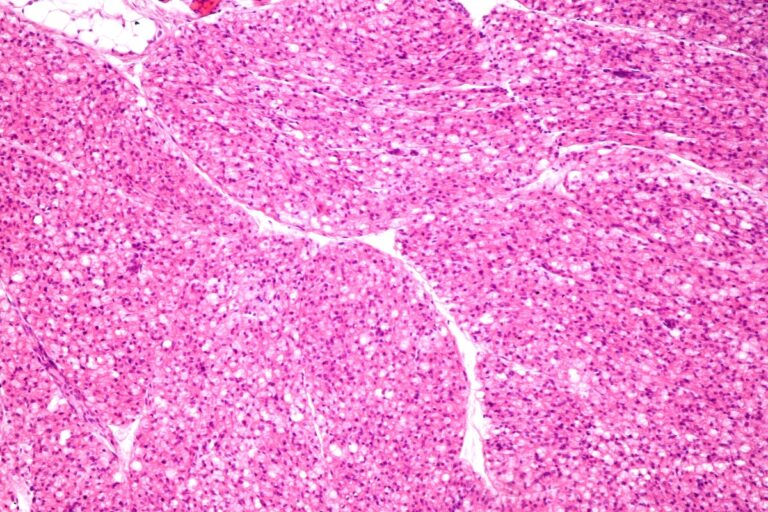

Τα κύτταρα του καφέ λίπους έχουν πάρα πολλά μιτοχόνδρια. Σε αυτά τα «εργοστάσια» παραγωγής ενέργειας του κυττάρου υπάρχει μια ειδική πρωτεΐνη, η UCP1 (θερμογενίνη), η οποία επιτρέπει να μετατρέπονται οι θερμίδες απευθείας σε θερμότητα και όχι σε «χρήσιμη» ενέργεια (ATP) όπως στα άλλα κύτταρα.